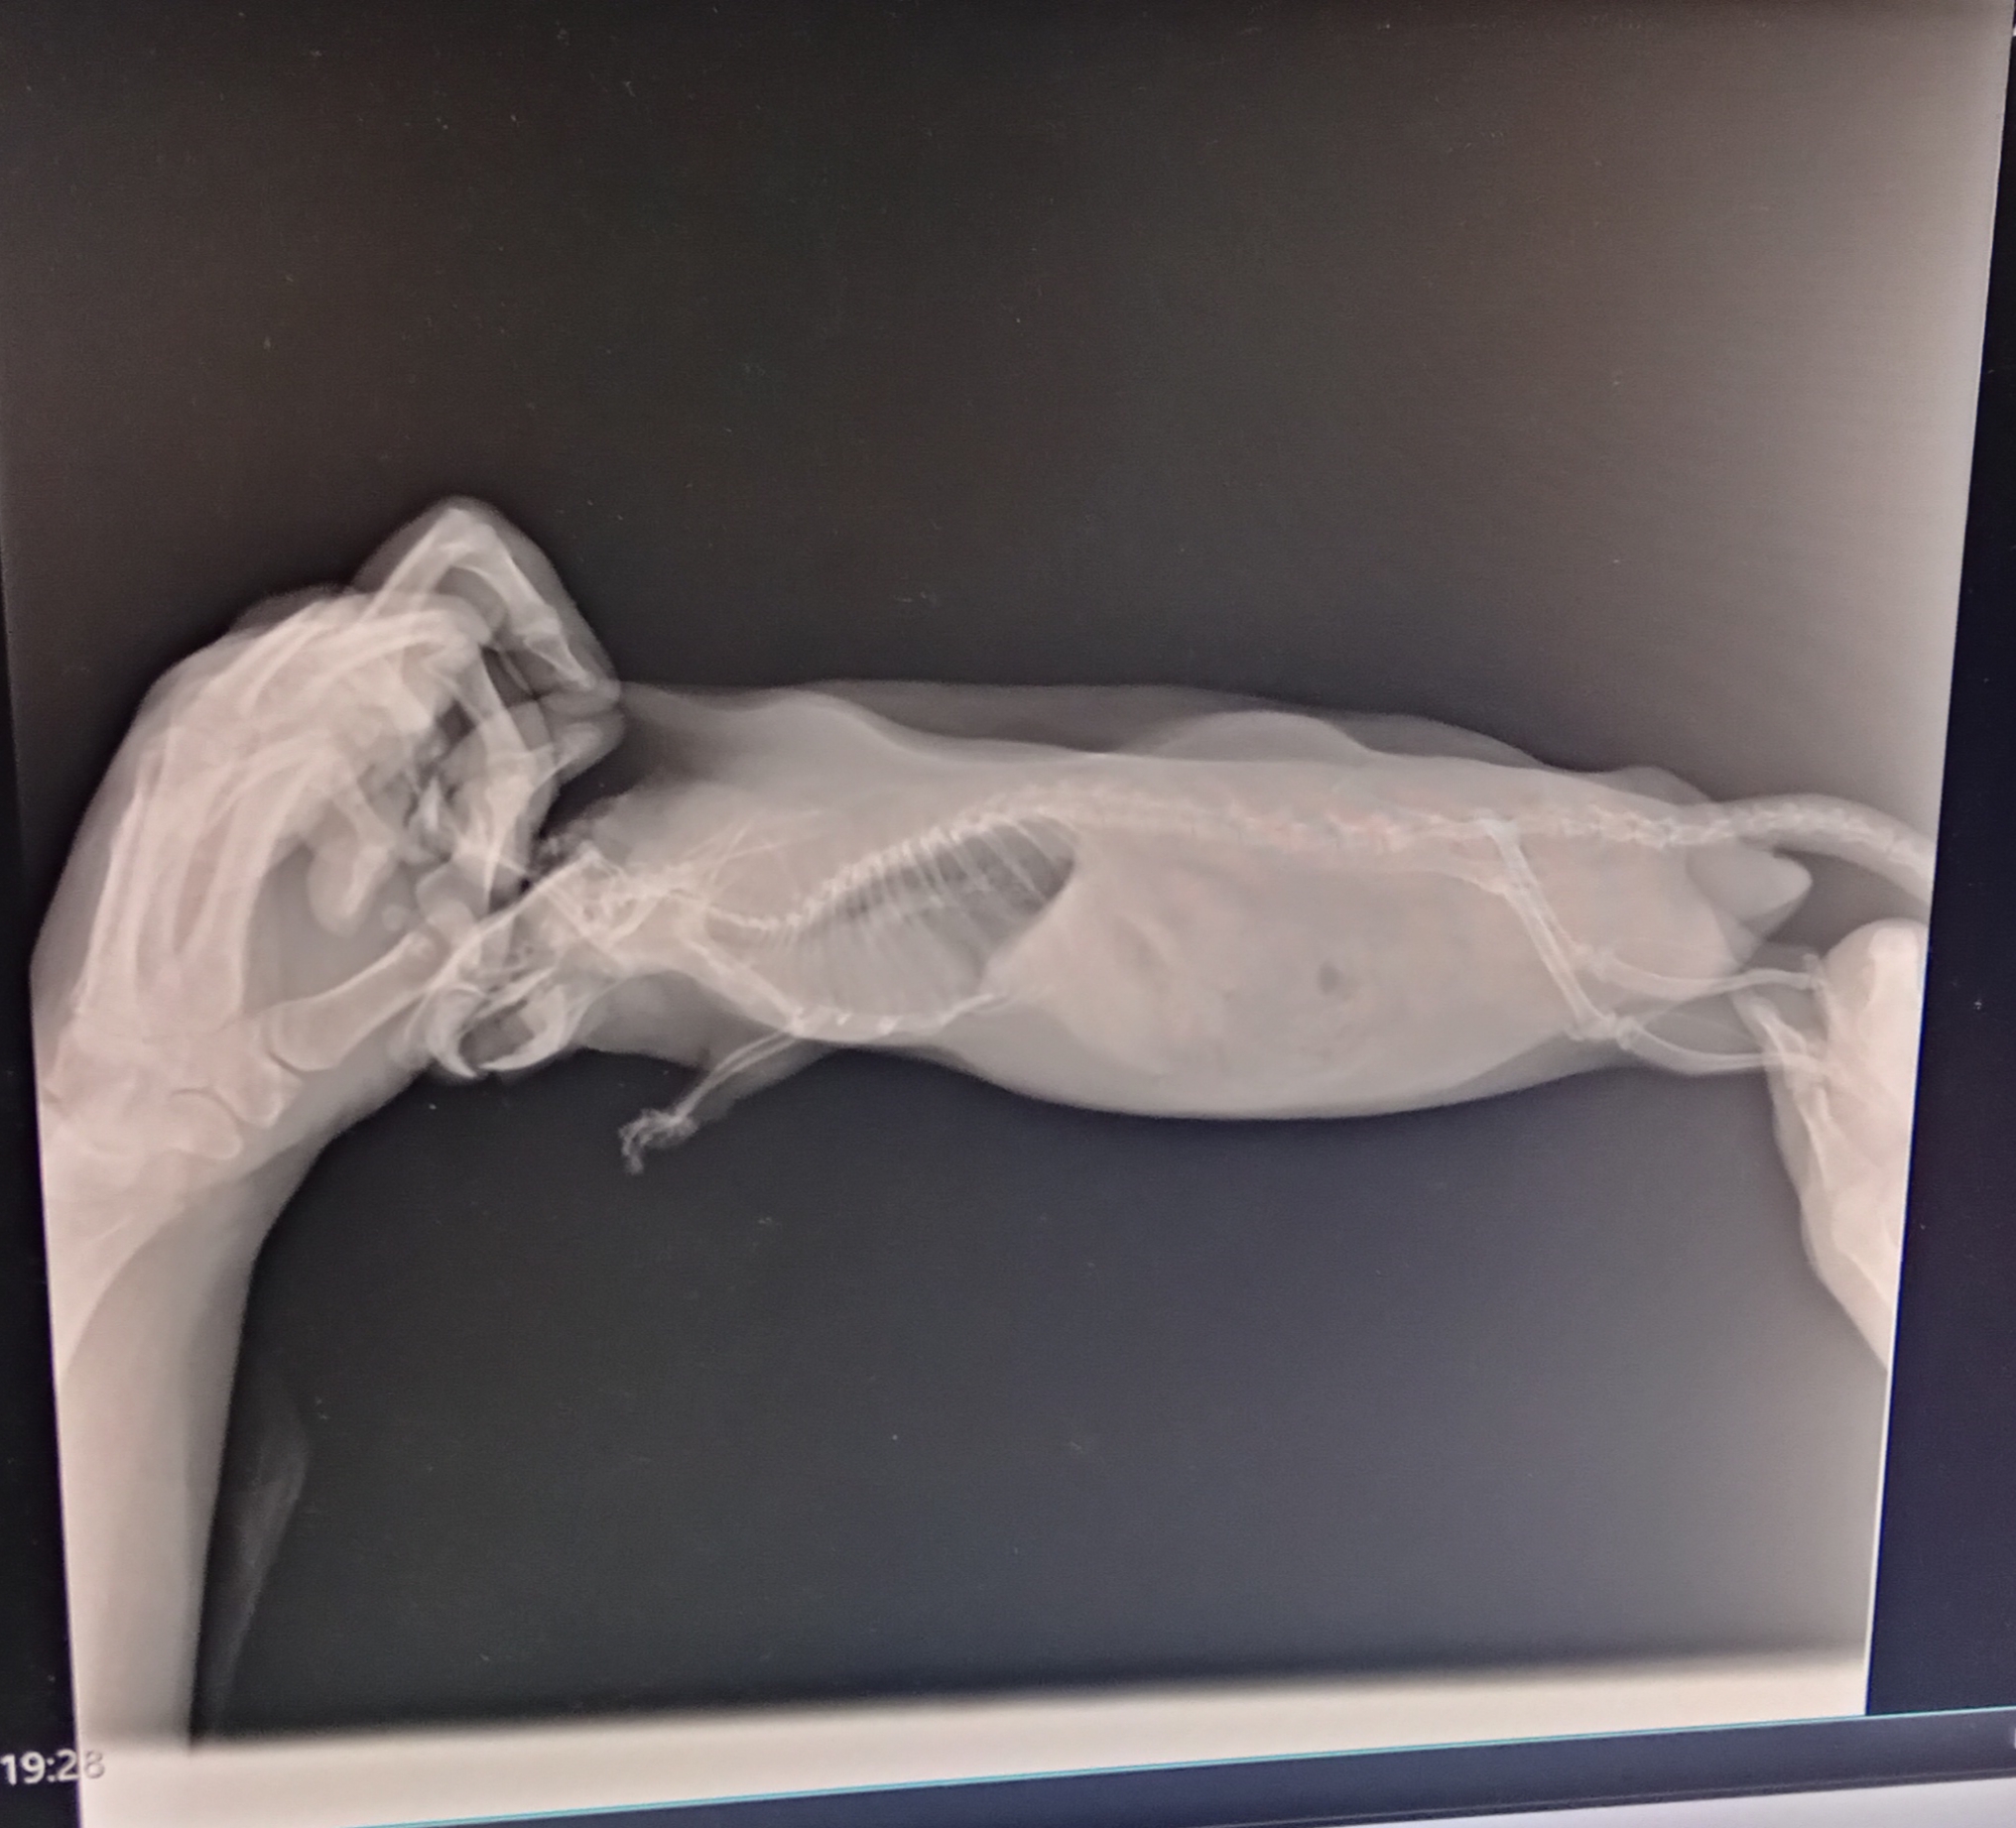

Здравствуйте. Очень нужна помощь. Крыса 1.7, заболел были сильные хрипы и сопли, дышал тяжело, шерсть взъерошена, нехватка кислорода (синели лапки и мордочка) . Были в клинике, что нам могли сделать, так это только рентген, так как специалиста по грызунам там нет. Назначили Амоксиклав и предположили, что возможно сердце (УЗИ не делают). Рекомендовали пропить ветмедин и мочегонку.

Антибиотик пропили только две недели, чихать -хрипеть перестал, но состояние не улучшается, только хуже становится. Похудел, можно сказать перестал есть, хотя до этого аппетит был как у трёх крыс вместе, апатичный, постоянно лежит голову свесив. Дыхание частое поверхностное. Из одного глаза то ли порфирин, то ли кровь.